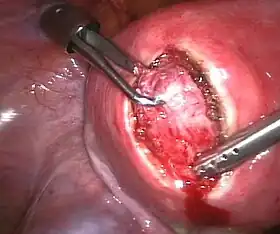

Submucosal fibroid in hysteroscopy

Submucosal fibroid in hysteroscopy Treatment of an intramural fibroid by laparoscopic surgery

Treatment of an intramural fibroid by laparoscopic surgery After treatment of an intramural fibroid by laparoscopic surgery